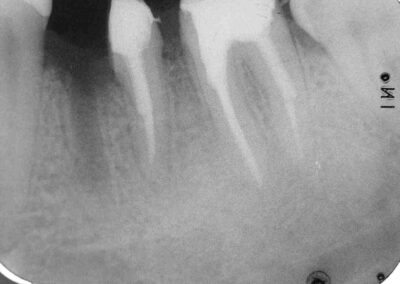

Ein knappes Jahr nach prothetischer Versorgung. Die Kronenränder sind übrigens nicht sondierbar überstehend. Der Erfahrene weiß, dass man die Diagnose „Überstehende Kronenränder“ aus dem Röntgenbild heraus nicht sicher stellen kann (Klick!)

Zum Glück hat die biologische Breite wieder das gemacht, was sie immer macht, wenn man – indikationsgerecht- Kronen mit rasierklingenscharf auslaufenden Kronenrändern eingliedert: Sie hat sich neu eingestellt!